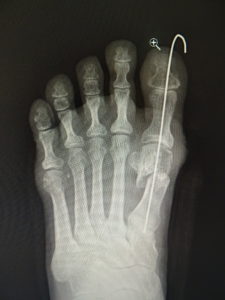

手術前 手術後4年

私は、ミッチェル変法ないしハモンド変法を行います(図6,7)。前日入院、腰椎麻酔(当日のみ臥床となります。)で一時間ほどの手術です。中足骨で骨切りを行い、長さも調節(多くはエジプト型足なので幾分短縮します。)しながら向きを矯正し、骨切り部をワイヤーで固定します。母趾内転筋の切離や、母趾外転筋の移行を検討します。中足骨頭部の種子骨を、正しい位置に戻して縫合します。術後は念のため、3週間ほど短いソックス型のギプスを装着しますが、術翌日から歩行訓練などの理学療法を行います。1ヵ月半ほどで骨癒合します。骨癒合が得られなかった症例はありません。2~3か月で普通に靴が履けます。入院期間は相談して決めればよいのですが、最短なら抜糸まで10日間、或いはギプス固定期間の3週間などが目安となります。

最近では、原則として固定ワイヤーは経皮的の一本のみとし、ワイヤーの先端は皮膚の外に出ているので、抜く時(術後3週間目)の患者さんの負担はほぼありません。こうすることによるデメリットはなく、むしろ術後成績は良くなっています。

(図6)

手術前 手術後

(図7)

真田理事長による手術の様子。外反母趾|症例 (左から 手術前、手術後、ワイヤ抜去後)